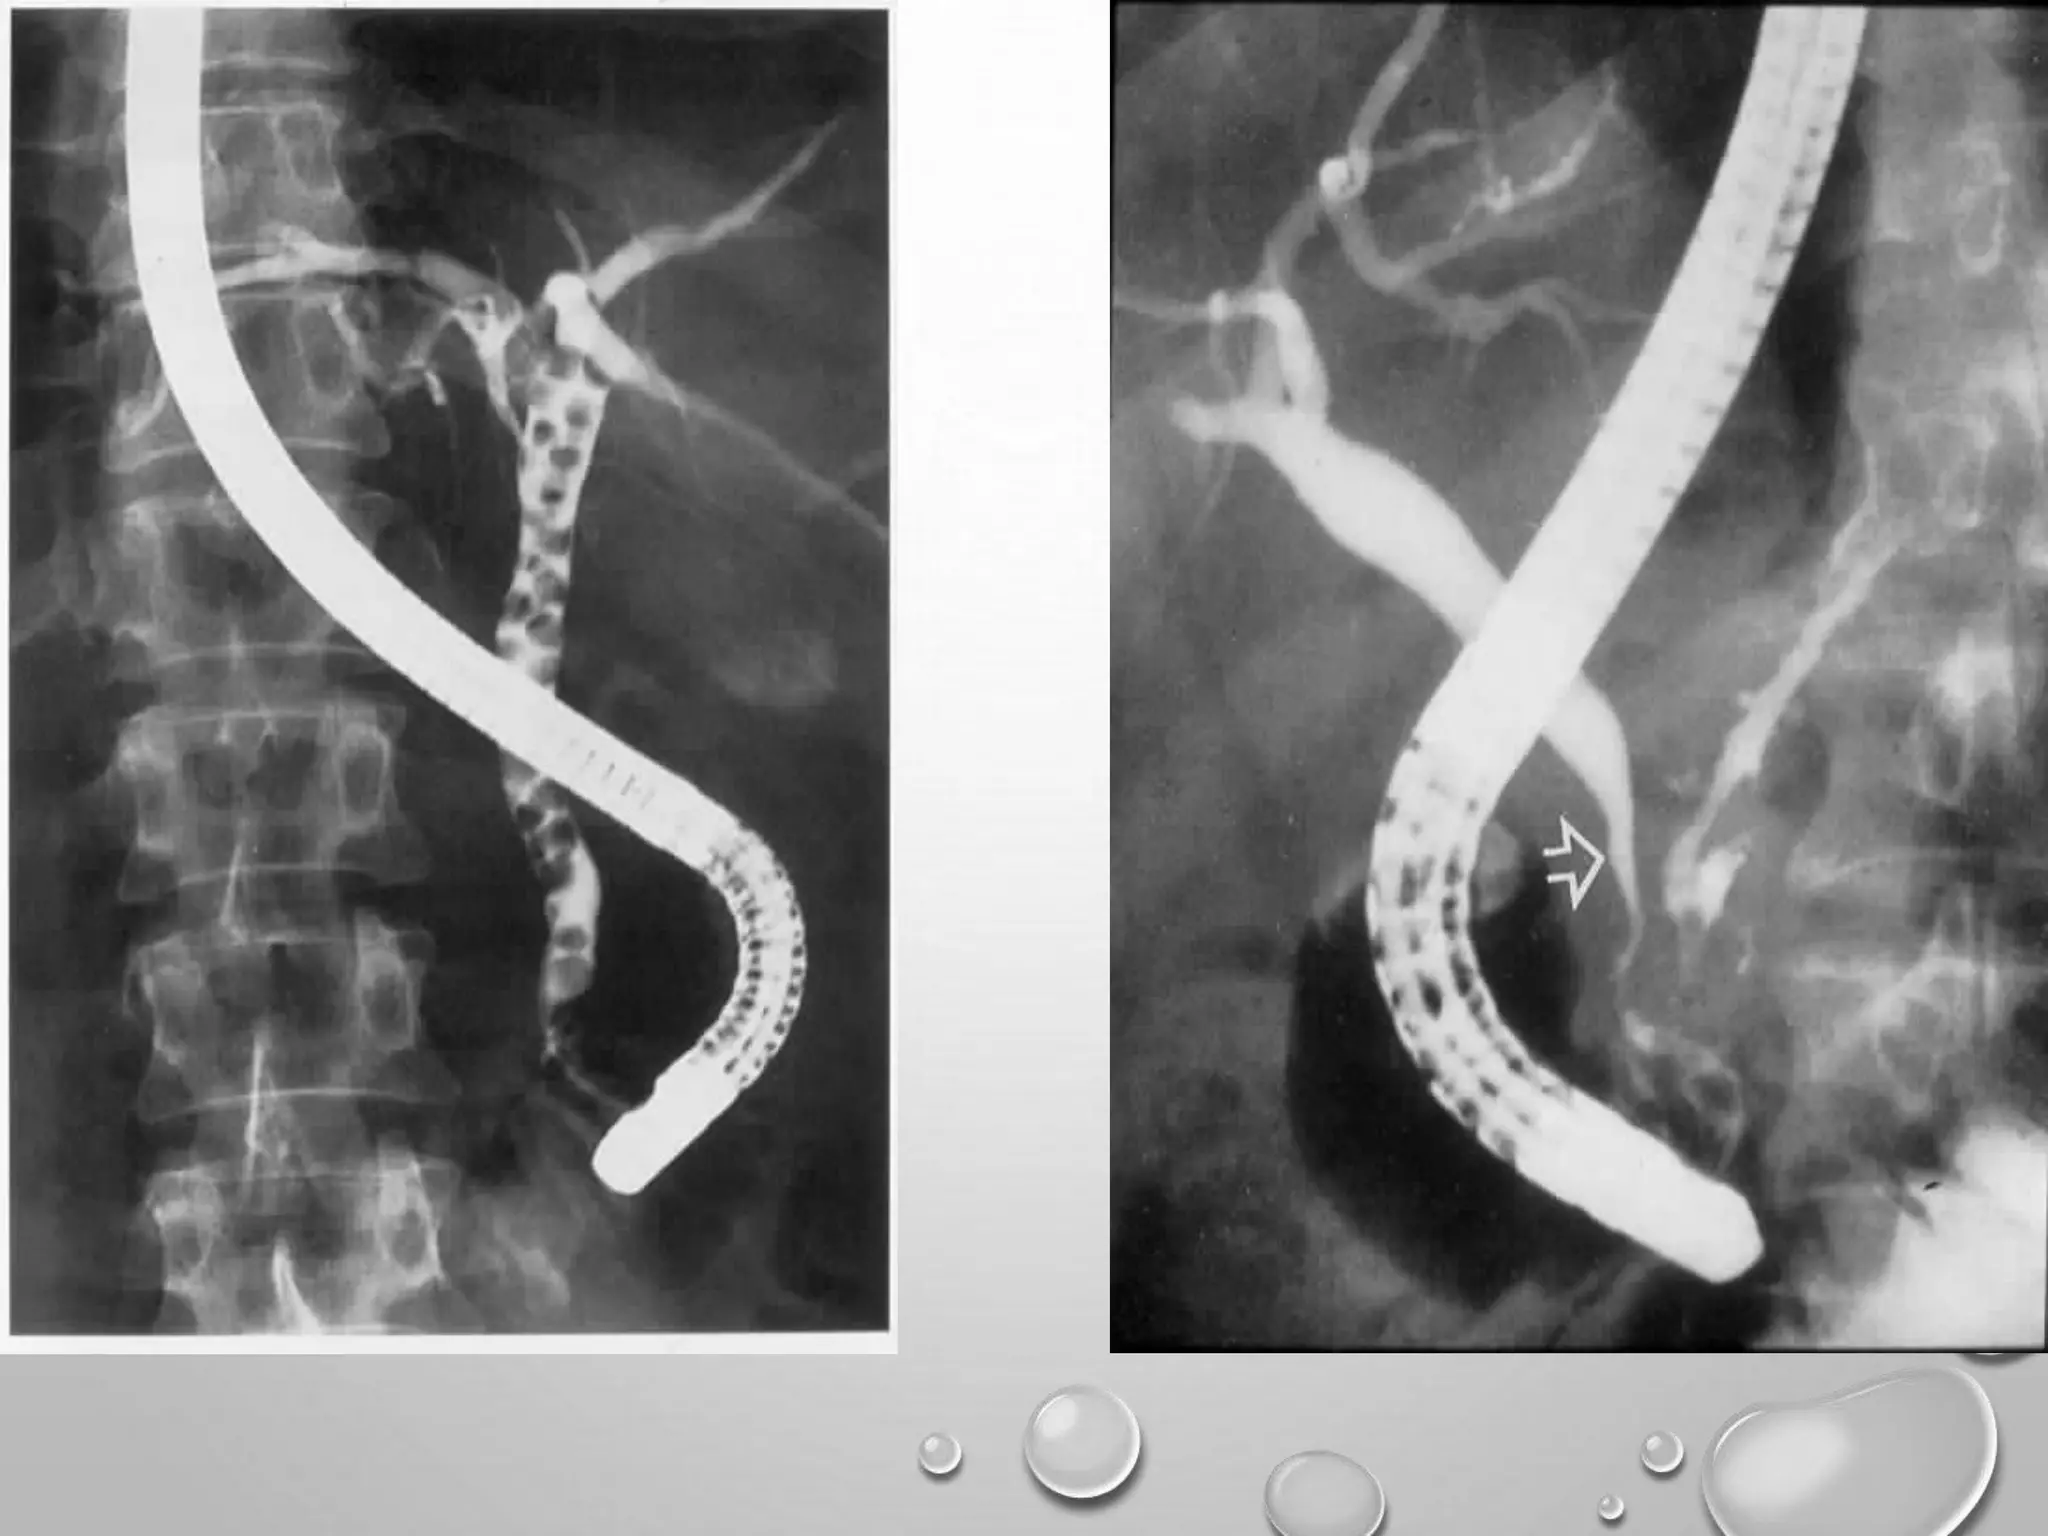

ERCP

 89%-98% sensitivity & 89%-100% specificity.

 ERCP is the procedure of choice in choledocholithiasis and in suspected

ampullary or duodenal lesions in ca pancreas.

 The diagnostic role of ERCP is to collect tissue for biopsy in periampullary

growths or brush cytology samples. The exact level of the block and the severity

of backpressure changes can also be ascertained.

ERCP  89%-98% sensitivity& 89%-100% specificity.  ERCP is the procedure of choice in choledocholithiasis and in suspected ampullary or duodenal lesions in ca pancreas.  The diagnostic role of ERCP is to collect tissue for biopsy in periampullary growths or brush cytology samples. The exact level of the block and the severity of backpressure changes can also be ascertained.